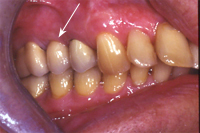

Da vertikal bei der Lücke zu wenig Eigenknochen vorhanden ist (Abb. 1), muss der Knochen mittels Sinuslift aufgebaut werden (Abb. 2). Das Resultat ist in Abb. 3 röntgenologisch und in Abb. 4 klinisch ersichtlich.